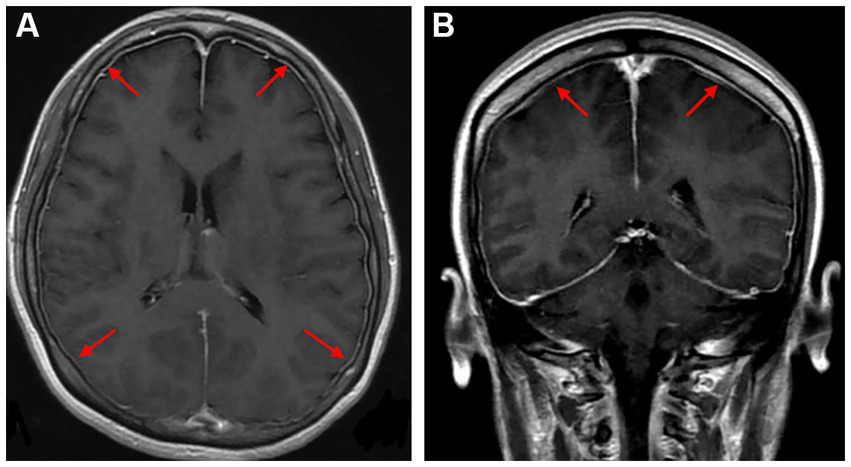

T2-FLAIR MRI revealed hyperintensities in the temporal, parietal, occipital lobes, left caudate nucleus, and right cerebellum (A). An MRA indicated multifocal, segmental, and diffuse narrowing of cerebral arteries (large and medium) [(B), red arrows]. After 10 days, complete remission of abnormalities was observed in a follow-up MRI compared to the previous signals (C). An MRA demonstrated significant cerebral artery recovery from diffuse segmental constriction (D).

Axial and coronal gadolinium-enhanced T1-weighted MR images showed diffuse pachymeningeal enhancement [(A,B), red arrows].